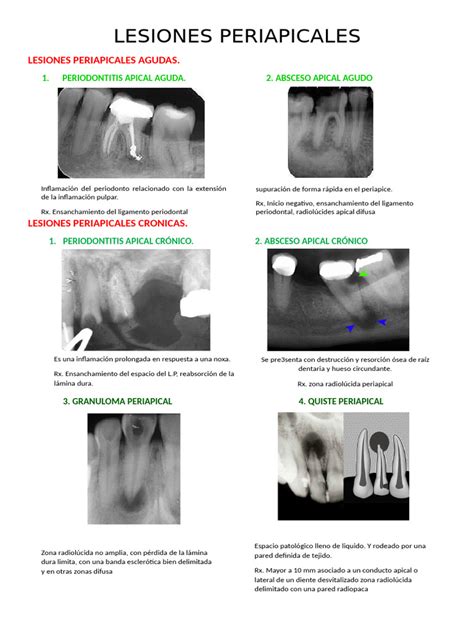

Lesiones Periapicales

Periodontitis Periapical Crónica (Granuloma Periapical)

La periodontitis periapical crónica (granuloma periapical) es una masa localizada de tejido inflamatorio crónico, con infiltrado inflamatorio agudo que contiene macrófagos y células polimorfonucleares; y infiltrado inflamatorio crónico que contiene linfocitos B y T. En la periodontitis periapical crónica, es común encontrar nidos de epitelio, formado por restos celulares epiteliales de Malassez, que tienen una capacidad latente para crecer.

Quiste Radicular

Son quistes que derivan de los restos epiteliales del ligamento periodontal (restos de Malassez) que inician su actividad al ser estimulados por un proceso inflamatorio, generalmente después de una necrosis pulpar. Se desarrollan cuando se produce inflamación pulpar en la región periapical o lateral radiculares, o bien tras la formación de un granuloma apical o lateral.

Cuando en un granuloma existen restos epiteliales de Malassez y estos son estimulados por un proceso inflamatorio, se inicia su proliferación hasta lograr delimitar una cavidad quística epitelial. Es el quiste más frecuente de los maxilares, representan más del 50%. Se desarrollan sobre todo en la dentición permanente, en los dientes temporales son muy infrecuentes, ya que suponen solamente del 0,5 al 3,3% del total de los quistes radiculares.